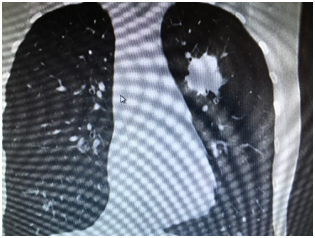

C’est le scanner thoracique avec injection d’iode qui oriente le diagnostic : nodule, trouble de la ventilation, ganglions etc…

Un scanner thoraco-abdominal injecté,